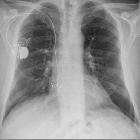

Adams-Stokes-Syndrom